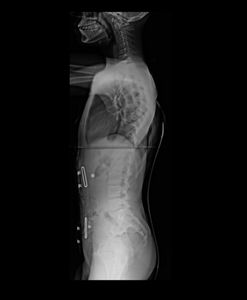

Há um ano, sua mãe reparou que ele começou a andar torto e comentou a situação comigo, Adriana, com quem ela trabalha ocasionalmente. Ofereci de levarmos o menino a um ortopedista particular e assim foi. Na consulta, o médico realizou exames de imagem (anexos a essa campanha) e, chocado, diagnosticou Juan com uma escoliose gravíssima, recomendando cirurgia em caráter de urgência.

Seguindo prescrição do ortopedista, Celia imediatamente providenciou colete de coluna, na AACD, na tentativa de segurar o quadro e prevenir que se agravasse. Em paralelo, levou Juan ao SUS e tomou conhecimento de que há uma fila enorme, e que a cirurgia poderia levar anos para acontecer -- tempo este que Juan não pode esperar.

De 1 ano para cá, desde o diagnóstico, a angulação da coluna de Juan tem piorado, apesar do uso do colete e do tratamento em sessões de RPG, e a cirurgia é inavitável.

Além da preocupação natural da família com o quadro geral, o grande receio é de que a coluna venha a comprometer o seu pulmão, já que Juan tem asma desde muito novo. Por isso, em razão da urgência e evolução gradativa do quadro, lançamos essa campanha! O valor arrecado será integralmente destinado à cirurgia e ao tratamento da escoliose de Juan.